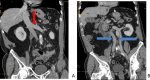

Duplication of the inferior vena cava is a rare malformation, normally without clinical impact, explained by abnormal development and regression of certain segments of the venous system during embryonic life. However, its presence and type should be systematically reported in the radiological report because of its potential implications for diagnostic and interventional procedures. This observation describes the case of a 77-year-old man with a complete asymmetric duplication of the inferior vena cava (type III IVC according to Natsis) that was incidentally discovered on CT-scan.